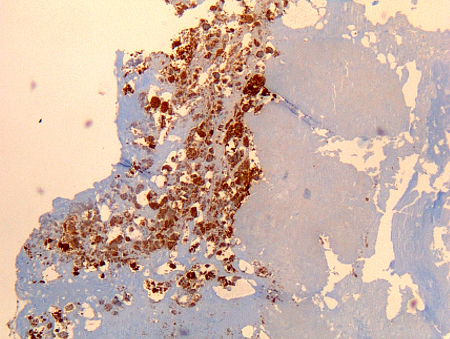

Osteíte por Coxiella burnetii: imuno-histoquímica: a coloração marrom identifica bactérias em monócitos/macrófagos.

Hubert Lepidi, Institut Hospitalo-Universitaire Méditerranée Infection